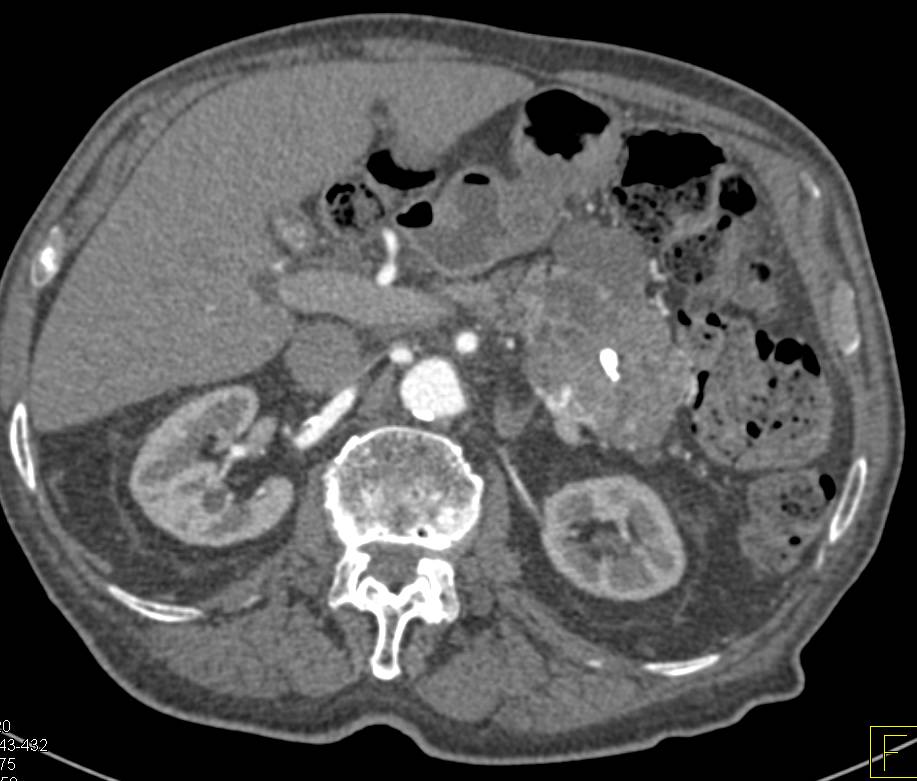

Acute Pancreatitis